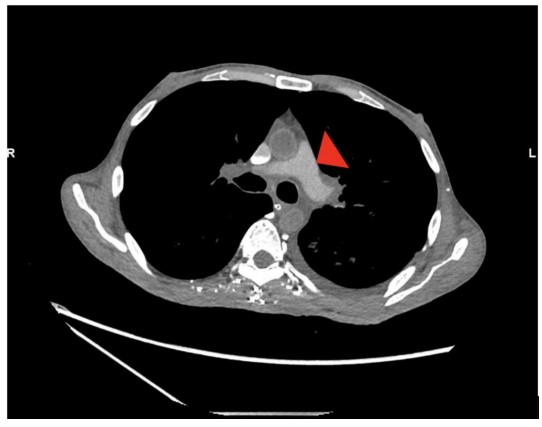

However, the acquisition revealed persistently poor opacification of the pulmonary trunk throughout the imaging interval (Fig. 1). The axial slices demonstrated pathognomonic features of circulatory collapse including dependent layering of contrast within the right ventricle, contrast pooling within inferior vena cava (IVC) and absence of contrast with in the left ventricle and aorta, indicating lack of forward flow (Fig. 2). Due to these highly suspicious findings, the examination was extended to the abdomen, which confirmed pooling of contrast within the hepatic veins (Fig. 3).